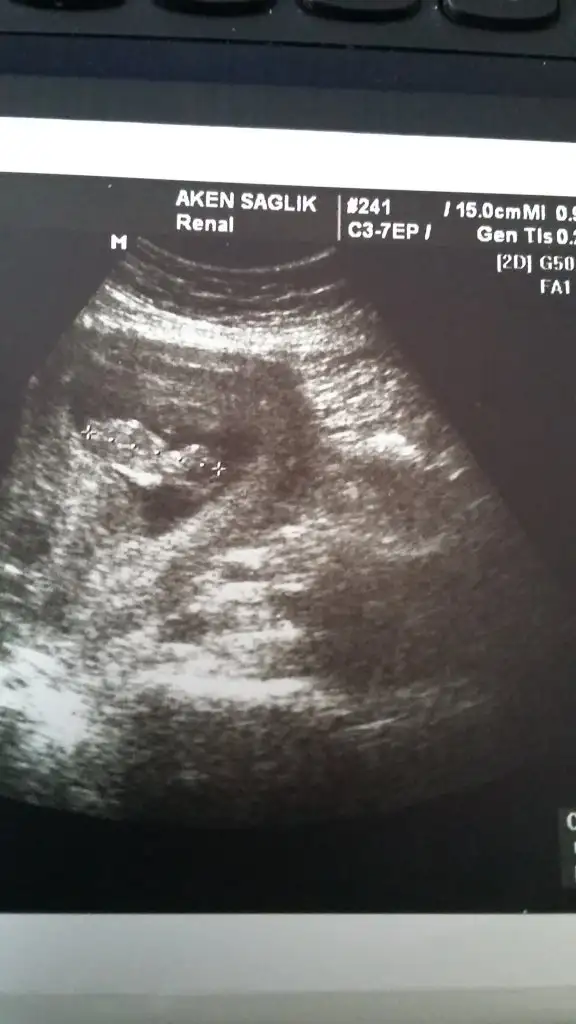

Kızlar ramziye göre plasentanın konumu önemli diye biliyorum.cinsiyeti netleşen arkadaşlar bir bakabilir misiniz?

Plasenta sağ üst veya sağ altta ise erkek

Plasenta sol üst veya sol altta ise kız diye biliyorum.tabi bu karından bakıldığında ters görünüyor ultrasonda,yani ultrasonda karından bakınca sağ sol gibi sol sağ gibi çıkıyor kağıda

Bakalım tutacak mı?

Plasenta nasıl anlaşılıyor ultrasonda. Bunu bi çözsem kavrıycam işi kimi et parçası gibi diyor kimi yay gibi diyor kimi parlaklık diyor